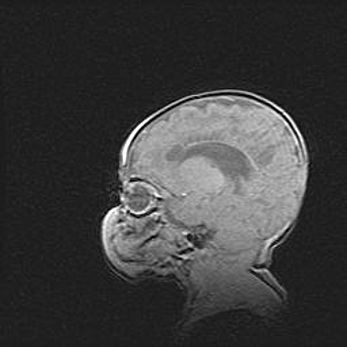

Сообщающаяся гидроцефалия. Кистозная энцефаломаляция головного мозга.

Возраст: 3 месяца 4 дня

Вес: 3100 г

Пол: женский

Окружность головы: 34 см

Срок гестации: 31 неделя

Кистозная энцефаломаляция головного мозга - одна из форм поражения головного мозга в детском возрасте. Характеризуется возникновением множественных и распространённых кист в коре, белом веществе и подкорковых образованиях головного мозга у плодов, новорождённых и детей раннего возраста. Развитие кистозной энцефаломаляции связано с внутриутробной асфиксией и гипотонией, родовой травмой, тромбозом синусов, пороками развития сосудов, инфекциями, сепсисом и другими причинами. Наиболее значимые инфекционные агенты: вирусы простого герпеса, цитомегалии, краснухи, токсоплазмы, энтеробактерии, золотистый стафилококк и другие.